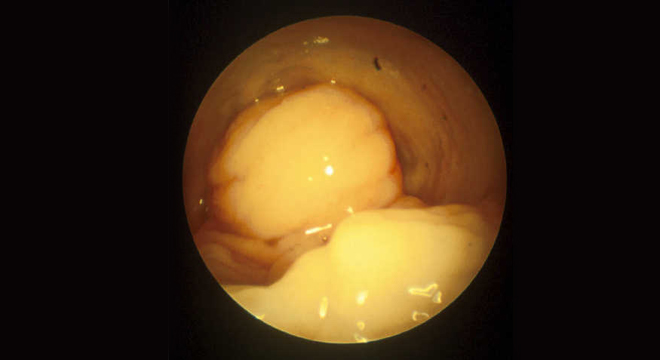

Harnröhrenverengung: Spiegelung der Harnröhre

• Spiegelung der Harnröhre (Urethroskopie)